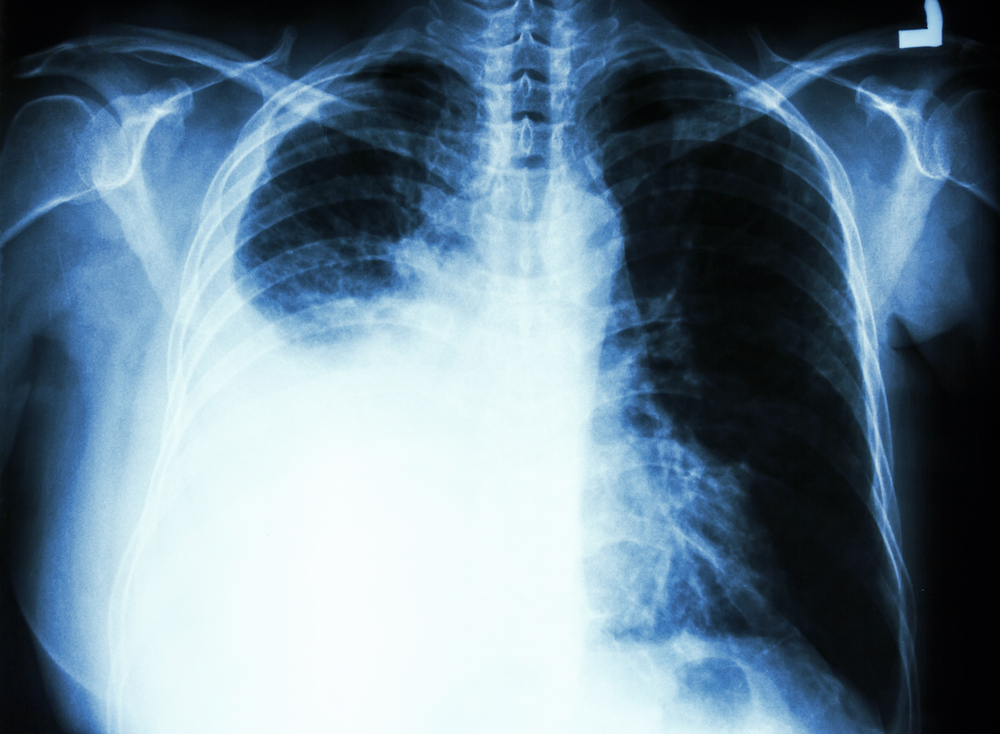

Các phương pháp thường được sử dụng để chẩn đoán và đánh giá tình trạng tràn dịch màng phổi là: